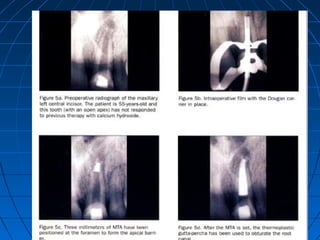

APEXIFICATION/APICAL BARRIER

TECHNIQUE

Prior to placement of MTA all necrotic debris should be

cleaned and canal bio mechanically prepared.

Manufacturer recommend medication of canal with

calcium hydroxide for 1 week with subsequent removal

using sodium hypochlorite. They also recommend a 3-5

thickness of MTA to be placed at apex.

If after placement of orthograde MTA

periapical surgery can not be excluded than

even after root end resection of 3 mm

additional root end filling need not be placed as

similar healing is shown with fresh MTA or set

MTA. It is also recommended to follow two

step apexification procedure that is after

placement of apical barrier a damp cotton

pellet in canal, temporize and allow material to

set for at least 4 hours or do obturation next

day.